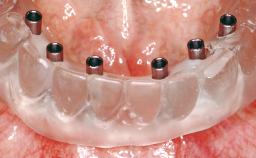

A 63-year-old female patient was referred to the University Medical Center in Groningen, Netherlands, for dental implant treatment. The patient had been edentulous in the upper jaw for 20 years. The remaining teeth in the lower jar had been removed two years before the consultation. The patient was wearing her first maxillary denture and her second mandibular denture; the latter was 1 year old at the time. The conventional upper denture had functioned satisfactorily for many years, but the patient complained about reduced stability and insufficient retention of her lower conventional denture. Her medical history revealed no significant findings. The intraoral examination revealed minor resorption of the maxillary alveolar process and extreme resorption of the mandibular alveolar process.

# of Implants 2

Prosthesis Type RDP

Defining Characteristics Fully edentulous lower jaw to be rehabilitated with an implant-borne removable overdenture